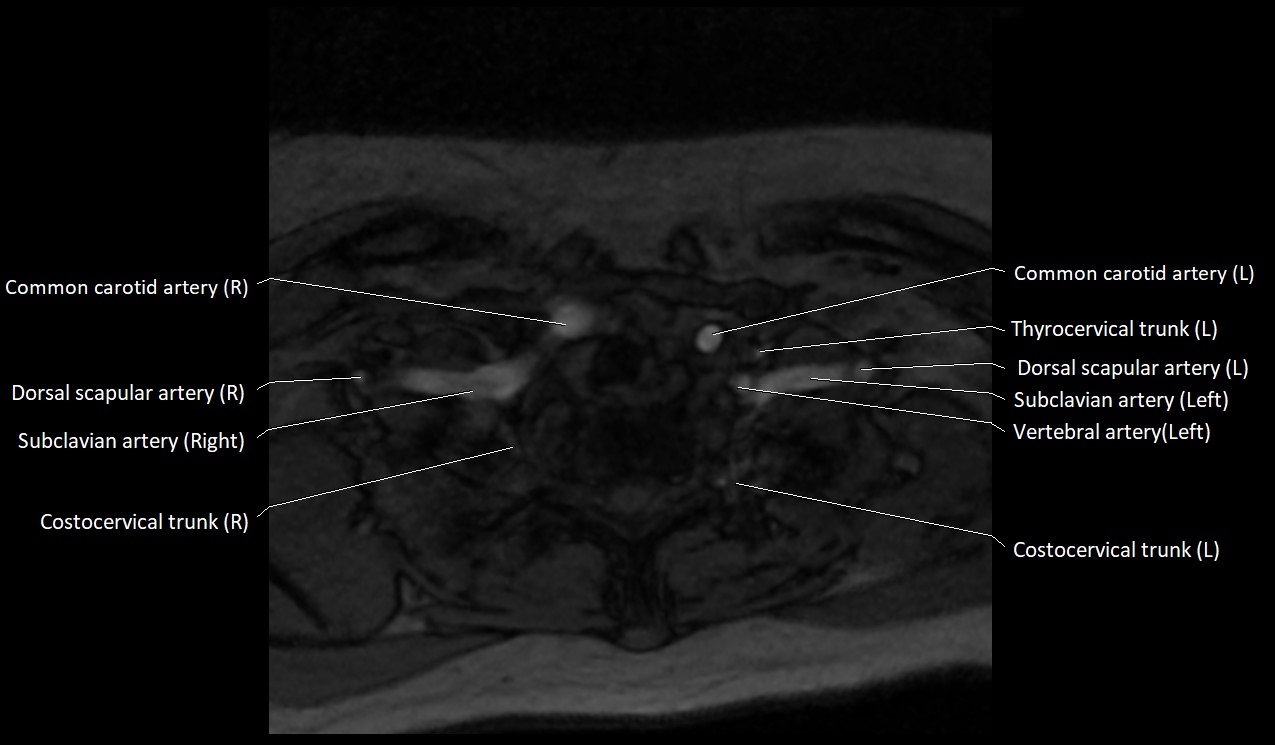

MRI Appearance:

• T1-Weighted Images:

• Appears as a tubular, hypointense (dark) structure relative to muscle

• May show flow void if the blood flow is fast

• T2-Weighted Images:

• Typically hypointense or isointense to muscle, but can be hyperintense if slow flow or stasis is present

CT image

image